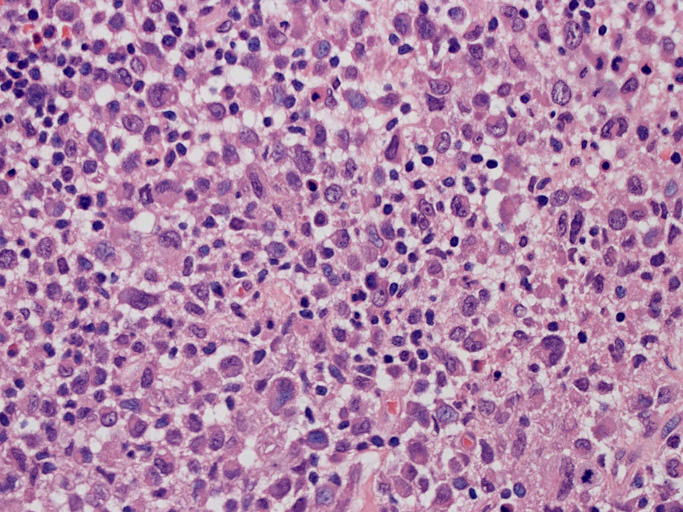

LCSの病理組織所見

Langerhans cell histiocytosisの高悪性度 variantで明らかな悪性像を示すLangerhans cellの腫瘍性増殖と定義される(WHO, 2008)

大型細胞の増殖よりなる腫瘍。縦溝,しわ,切れ込みのある核をもった大型細胞も出現する。クロマチンは顆粒状で核小体も明瞭である。核分裂は >50/10hpfと多い。eosinophilsは少ない。壊死が多発することがある。未分化ないし低分化な細胞像, 組織所見のため鑑別診断は多岐にわたり、的確な免疫染色を行う必要がある。

皮膚に異型細胞の浸潤がみられる。異型細胞は表皮内に浸潤するほか、表皮真皮境界部, 真皮, 皮下脂肪組織にもびまん, 結節様の浸潤所見を示す。血管周囲に浸潤、集蔟する所見も多く見られる。 増殖浸潤細胞の核には類円形や腎臓形, またはへこみ, 切れ込み, 溝などを有する多型な核が認められる。クロマチンは粗でvesicularな核が多い。核小体の明らかな核もある。好エオジン性の核内封入体様構造も少数に見られた。mitosisは容易に認められる。hyperchromaticな多型核, bizzarreな細胞が高頻度に認められ異型度は高いと考えられる。細胞質は境界不明瞭, 淡明または泡沫様の 好エオジン性胞体である。